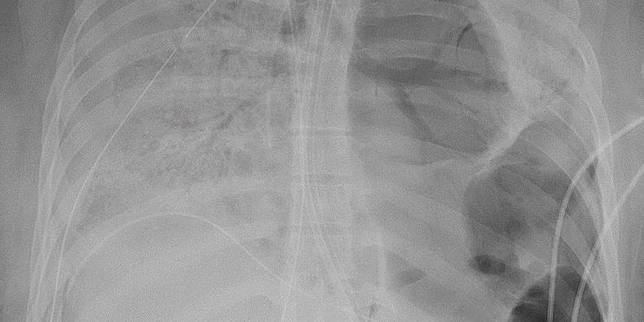

Pada awal Juni, paru-parunya menunjukkan kerusakan parah. Ia kemudian didaftarkan untuk mendapat transplantasi paru-paru ganda.

Kerusakan paru-paru pada perempuan itu, dikatakan Bharat, adalah salah satu yang terburuk yang pernah dilihatnya.